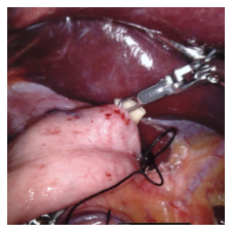

Endoscopic video recordings are widely used in minimally invasive robot-assisted surgery, but when the endoscope is outside the patient's body, it can capture irrelevant segments that may contain sensitive information. To address this, we propose a framework that accurately detects out-of-body frames in surgical videos by leveraging self-supervision with minimal data labels. We use a massive amount of unlabeled endoscopic images to learn meaningful representations in a self-supervised manner. Our approach, which involves pre-training on an auxiliary task and fine-tuning with limited supervision, outperforms previous methods for detecting out-of-body frames in surgical videos captured from da Vinci X and Xi surgical systems. The average F1 scores range from 96.00 to 98.02. Remarkably, using only 5% of the training labels, our approach still maintains an average F1 score performance above 97, outperforming fully-supervised methods with 95% fewer labels. These results demonstrate the potential of our framework to facilitate the safe handling of surgical video recordings and enhance data privacy protection in minimally invasive surgery.